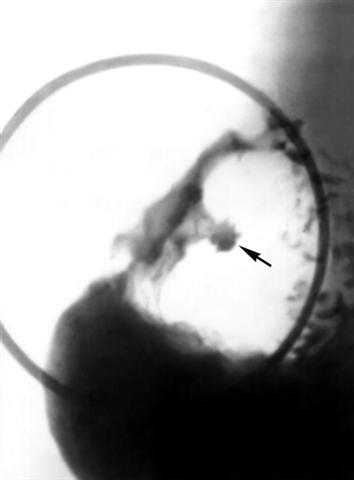

Рис. 1а). Прицельные рентгенограммы (в разных проекциях) луковицы двенадцатиперстной кишки при язвенной болезни: профильная, или контурная, ниша на задней стенке луковицы (указана стрелкой) с воспалительным валом в виде просветления.